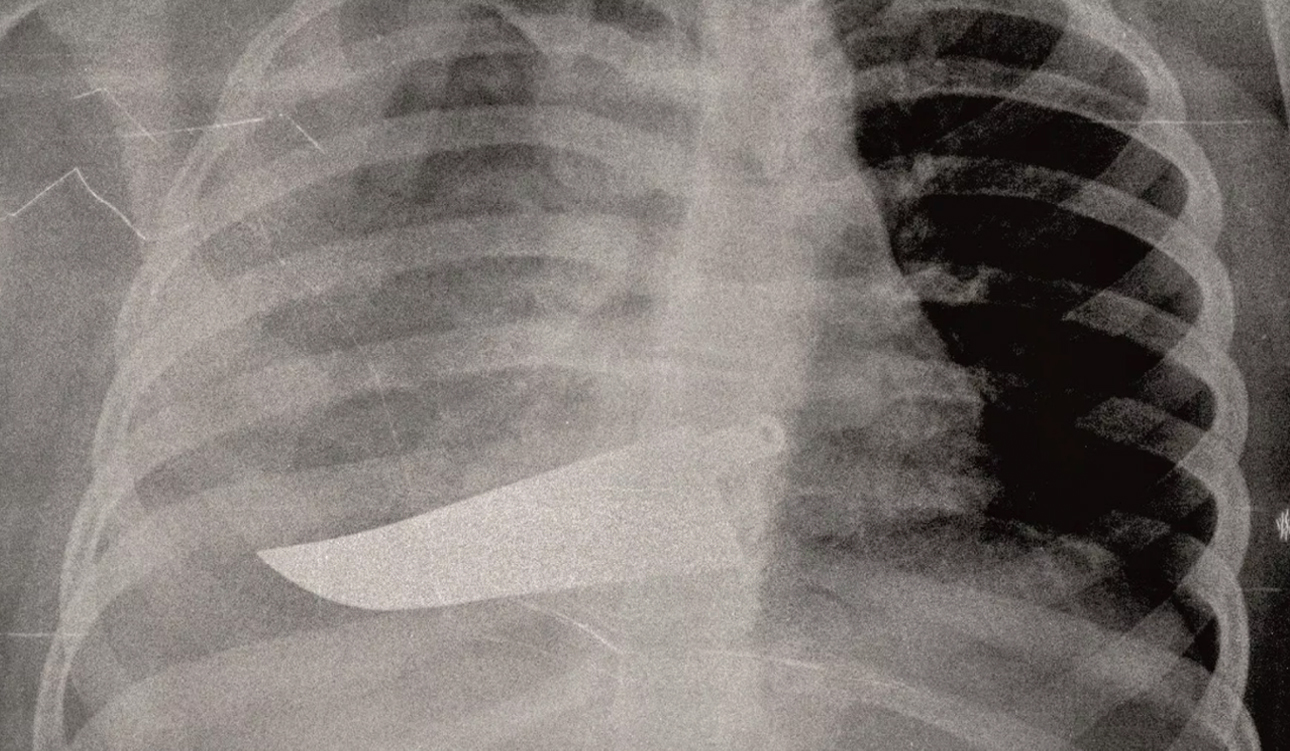

«Εδώ είναι η καθημερινή φρίκη που αντικρίζουμε στα έκτακτα περιστατικά. Συχνά οι τραυματισμένες γυναίκες δεν έχουν τη δύναμη να πουν τι τους έχει συμβεί, αλλά τα σώματά τους και τα τραύματά τους μιλούν από μόνα τους». Η ιατρός περιγράφει τα συνήθη: «Σπασμένα οστά σε μύτη, χέρια, πόδια, πληγές από μαχαιριές, εγκαύματα, μελανιές και άλλα σημάδια στραγγαλισμού». Αλλά και τα ασυνήθη: «Μέχρι και με ένα μαχαίρι καρφωμένο στην πλάτη της μας ήρθε μια γυναίκα».

Ετσι η Βανταντόρι αποφάσισε να εκθέσει «εικόνες από έναν αόρατο πόλεμο που διεξάγεται καθημερινώς πίσω από τους τοίχους των σπιτιών», δηλαδή τις ανώνυμες ακτινογραφίες οι οποίες δείχνουν τα βασανιστήρια που υπέστησαν οι γυναίκες «από συζύγους, πρώην συζύγους, συντρόφους». Η ρεπόρτερ του ιταλικού φύλλου χαρακτηρίζει την έκθεση «ακραία και τραγική».

«Ολα αυτά τα χρόνια στην πρώτης γραμμής κλινική ιατρική, έχω δει χιλιάδες ακτινογραφίες γυναικών με κάθε είδους τραύματα, ακόμη και πολύ σοβαρά. Πολλές από αυτές τις γυναίκες αρνήθηκαν ότι τα τραύματά τους τα προξένησαν οι σύζυγοι ή άλλα μέλη της οικογενείας τους. Η άρνησή τους σχετίζεται με αρνητικά συναισθήματα, με φόβο, ντροπή, αγωνία για την τύχη των παιδιών τους ή και για τη ζωή τους ακόμη». Η ιατρός περιέγραψε και το τρομερό περιστατικό με το καρφωμένο στην πλάτη μαχαίρι.